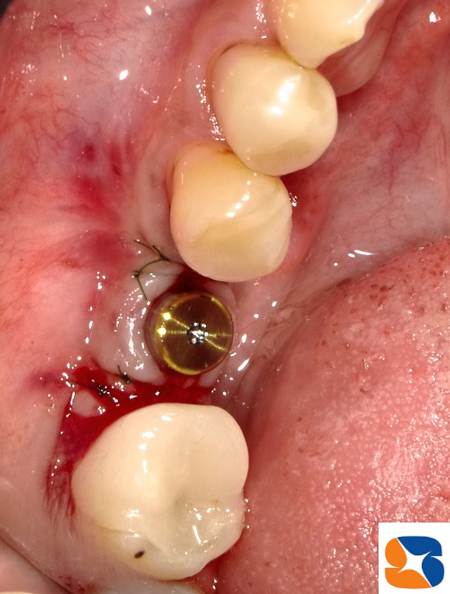

ところが、欠損部の横の歯が、かなり後ろに傾いています。このようなケースでは、植立したインプラントの角度や深度にミスが生じやすくなります。そこで、ノーベルバイオケア社製の「サージカルガイド」を使用して確実な手術を行う計画をたてました。

ノーベルクリニシャンを使って、インプラントの適正な植立位置(角度、深さ)や仮想の歯をシュミレーションします。このデーターをノーベルガイド社に送信して、ガイドを注文しました。

出来上がったサージカルガイドを使って手術が始まりました。

ガイドを使用すれば、神経を傷つけたり、アゴを突き抜くような事故がなくなるので、患者様も安心して手術を受けて頂けます。

サージカルガイドどは、ドリル器具がわずか1㍉、わずか1°の角度もズレることなく安心・安全に手術を進めるための医療器具です(当院では追加料金なし)。

自己血液を使って、自家血小板含有フィブリンゲル(CGF)を院内で製作します。

これを、抜歯痕やインプラント整形部に添加させて痛みや腫れを抑えます。

新発売されたばかりの「On1ベースアバットメント」を使って、無事に完了しました。